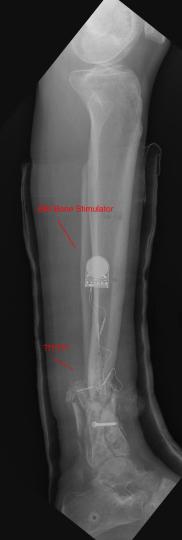

Postoperative (12th) images of left ankle

The images displayed here were created at various appointments following surgery performed by Dr. Daniel Saunders. In the X-Ray you can see

where Dr. Saunders has removed the fibula plate, joined the tibia and fibula with a screw, built-up the area of the tibia where previously

there was considerable absence of bone and lastly added the EBI OsteoGen-M Bone Stimulator (dual lead). The photos show the left side site

where the fibula plate was removed, the top site where donor bone, bone filler material and the stimulator were added and the right side

where the tissue has burst because of swelling. Liam was placed on an IV drip of Vancomycin following surgery to combat the potential onset

of Osteomyelitis. The image of the cast includes the fibula plate that was removed during surgery. The next images were taken later and show

that the staples and stitches were removed. In one of the images, you can see Liam's wife Madeline helping with leg cleanup and in one image

can be seen the EBI representative after being put to work (holding up the left leg while the latest cast cures) by Dr. Saunders. Later shots show

a healing tissue burst site with some overgrowth and Dr. Saunders cauterizing the overgrowth. Bones shifting too much (shown in X-Rays). The

last images are of the left ankle prior to the 13th surgery.